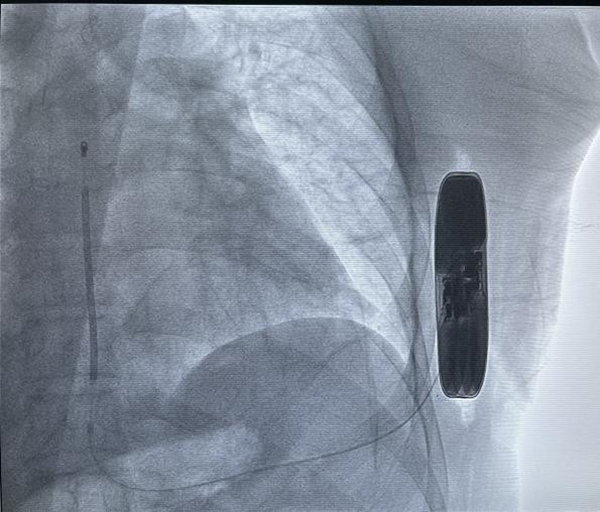

SICD主要由脈沖發(fā)生器、電極導線組成,與頸靜脈植入型心律轉復除顫器(TV-ICD)。不同的是,SICD的脈沖發(fā)生器經(jīng)皮下置于左側胸壁,電極是由兩個感知電極及一個電擊線圈組成,經(jīng)皮下置于胸骨旁。作為全皮下心臟除顫系統(tǒng),SICD可在一定程度上避免與靜脈導線相關的圍手術期及其長期并發(fā)癥,且手術過程不需要在透視下進行。SICD的適應人群主要包括:伴有靜脈畸形或梗阻不適合經(jīng)靜脈行心臟轉復除顫器的兒童、感染風險大及有猝死風險的年輕心律失;颊(如Brugada綜合征、長QT綜合征等)。